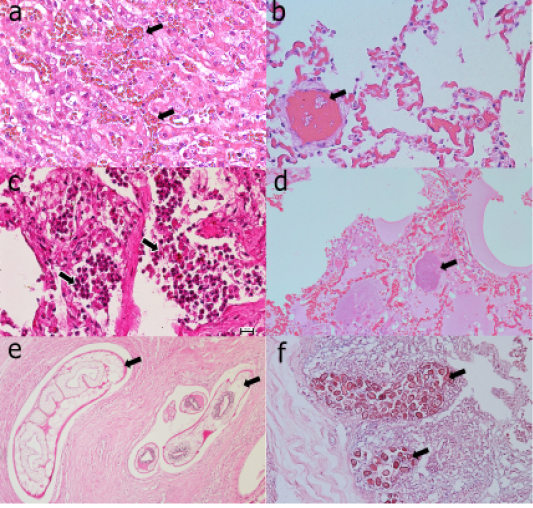

Figure 1

Common histopathological lesions observed in septicaemia (a-b), bacterial pneumonia (c-d), and gastrointestinal parasitic infection (e-f). (a) congestion (arrows) of liver. (b) disseminated intravascular coagulation (arrows) in the lungs.(c) presence of inflammatory cells (arrows) in the alveolar spaces. (d) presence of bacterial colonies (arrow) and pulmonary oedema. (e) cross section of helminthes (arrows) in the gastrointestinal tract. (f) presence of different stages of protozoa (arrows) in the intestinal mucosa.